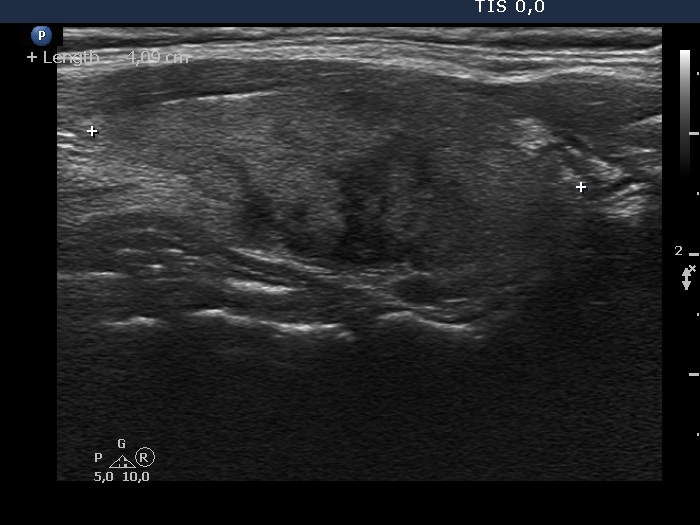

Follow-up investigation 4 weeks after the first visit (ultrasonographic picture 4)

Right lobe, longitudinal scan

Left lobe, longitudinal scan. The hypoechoic areas have blurred borders.